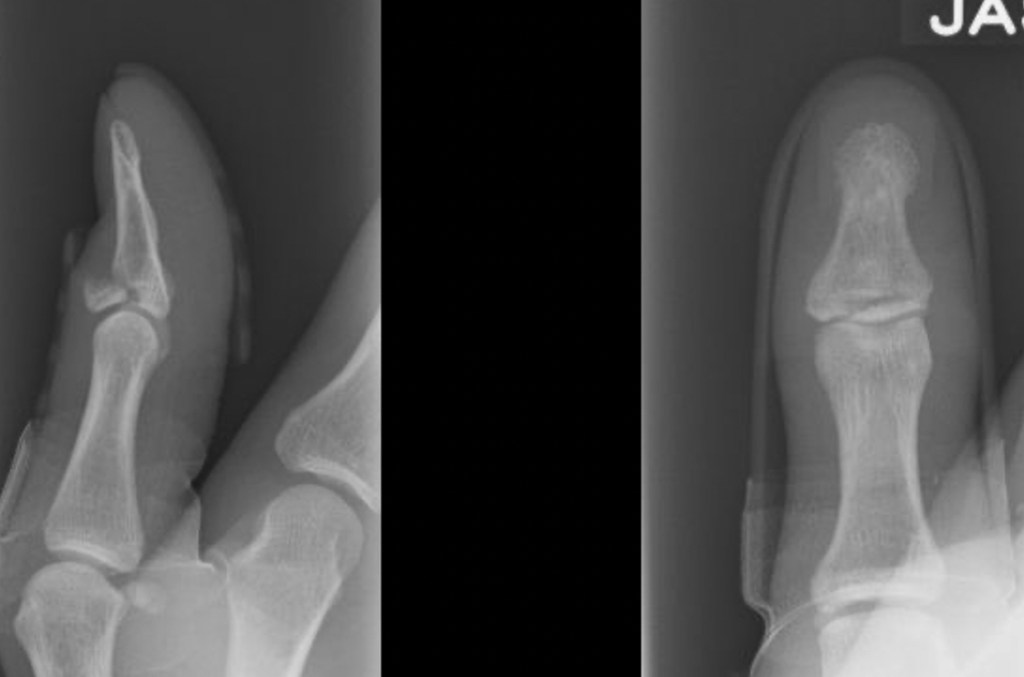

The diagnosis is made clinically on the basis of the mechanism of injury, and the presence of tenderness over the end finger joint, with an inability to fully straighten the finger (this is known as an extensor lag). An X-ray will often be performed to look for any fractures.

Mallet fingers are generally STABLE injuries – there is a very small risk of dislocation of the joint associated with a simple mallet injury. The presence of a fracture on xray can indicate a more severe injury, and if the bony fragment is large, the injury should be considered potentially UNSTABLE. This distinction is important because an unstable injury sometimes needs an operation to make sure that the end finger joint does not dislocate.